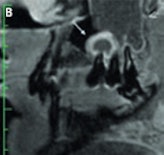

High-resolution (3-tesla) MRI of a patient with an inflammatory endoperiodontal lesion at tooth 017 (arrow). Sagittal T2-weighted space (A), T1-weighted plus gadolinium (B). Images courtesy of Dr. Stefan Rohde.Imaging in these patients is usually performed with 2D panoramic radiography, CT, or CBCT. However, MRI may represent a complementary imaging technique to visualize particular pathological processes, especially inflammatory disease of the periodontal space, or teeth vascularization after trauma, he said. His presentation focused on the potential of high-resolution MRI in this new field and compared it with CT and CBCT.

T2-weighted (A) and contrast-enhanced T1-weighted images (B) of a patient with a periapical granuloma at tooth 015 (arrow) and odontogenic sinusitis in the maxillary sinus (open arrow). Images courtesy of Dr. Stefan Rohde."MRI of the dental apparatus is technically challenging as the bony structures of the mandible and teeth give only little or no MR signal," Rohde said. "Another concern is the problem of air content and metal artifacts in the oral cavity that limit the use of MRI in this special setting. As a principal finding of our experiments, MRI proved to be superior to MDCT [multidetector-row CT] and to CBCT in visualizing periodontal structures like the periodontal space and the adjacent lamina dura. Surprisingly, even cortical and trabecular bone were displayed better with MRI than with MDCT and CBCT. Therefore, I believe that MRI could become an important complementary imaging source of the jaw and teeth apparatus in pathologies of tissue investing and supporting the teeth."